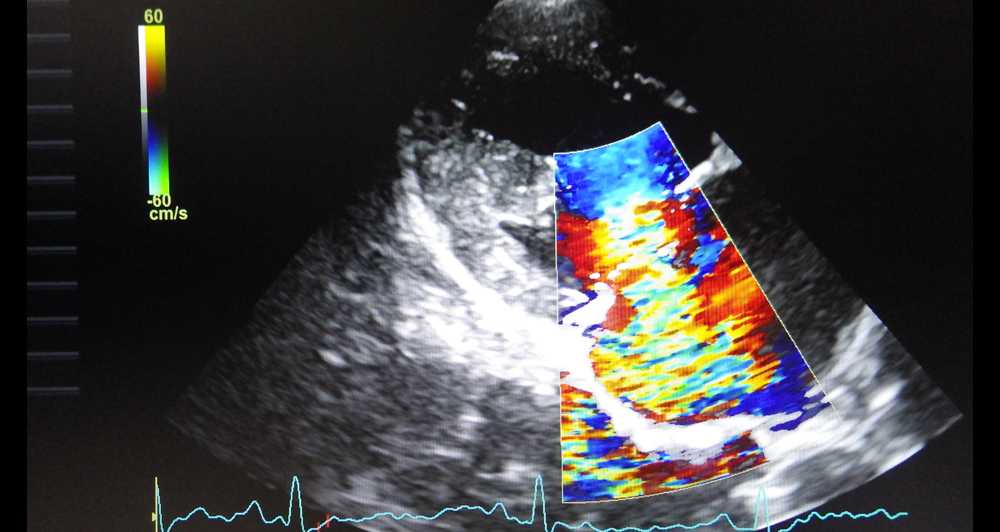

心臓の中の血液の逆流量が少ない場合は無症状ですが、逆流量が多くなると運動不耐性や発咳などの症状が現れます。

重症になるとうっ血性心不全を起こして、肺に水がたまったり(肺水腫)、呼吸状態が悪くなったりして、失神を起こしたりすることもあります。